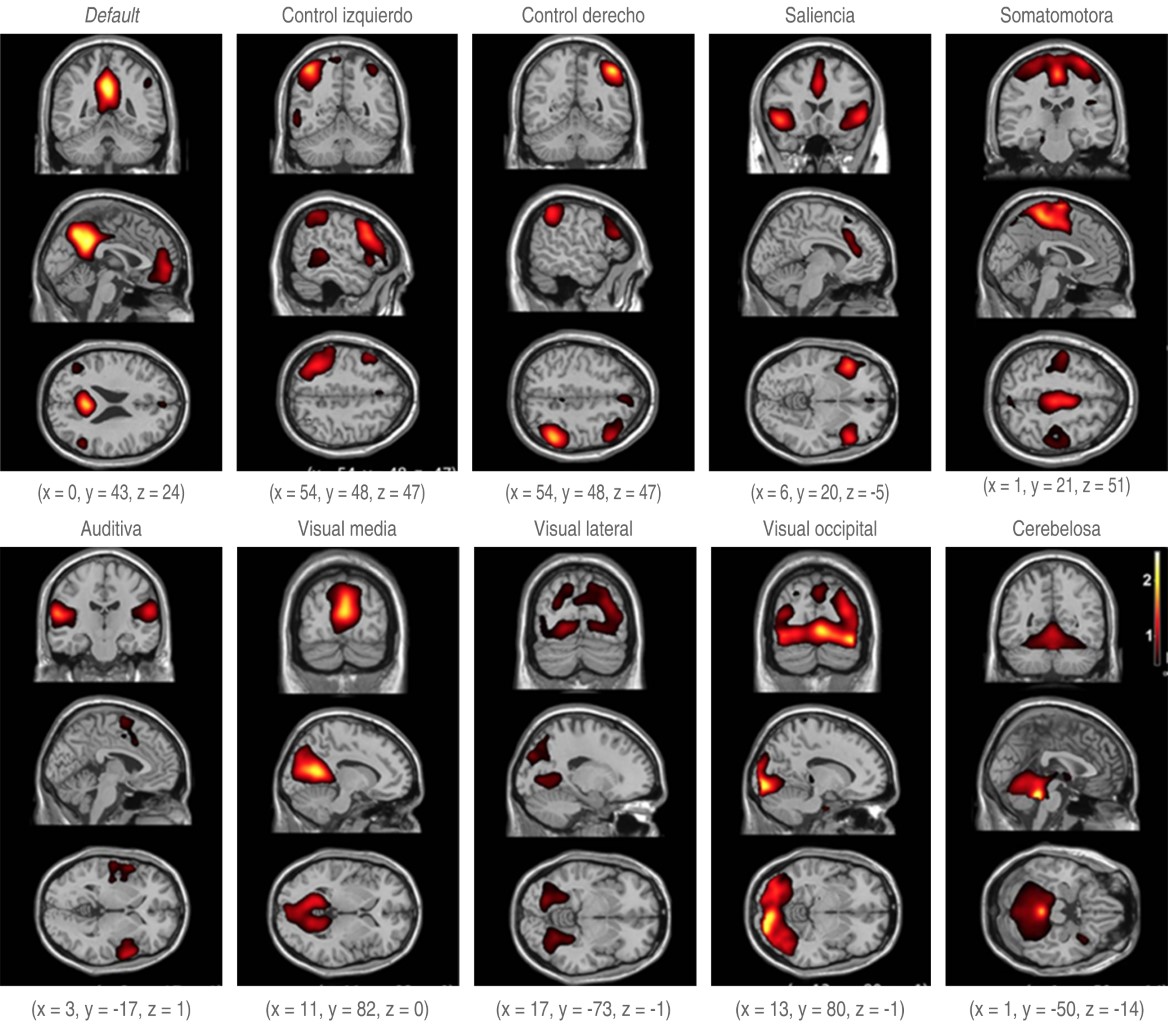

La primera de estas redes fue reconocida y estudiada en 1995 por Biswal y colaboradores. Estos autores describieron la red de default, después de la cual, se fueron descubriendo más redes cerebrales; siete de estas redes se aceptan como fundamentales, aun cuando no hay un consenso universal al respecto ni a su número final. A continuación se describen estas siete redes:

• 1. Red de default o frontoparietal medial: incluye las cortezas prefrontal media, posterior del cíngulo y parietal inferior junto con el hipocampo. Tiene como labor la recolección de recuerdos, imaginación, planes a futuro y divagaciones mentales.

• 2. Red de control derecha e izquierda: está compuesta por la corteza lateral prefrontal, el lóbulo parietal inferior, gran parte de la circunvolución del cíngulo, la región de la precuña, el tálamo dorsomedial y la cabeza del núcleo caudado. Esta red ejerce el control de la información que fluye a través del cerebro, incluyendo la consciencia y memoria. Está en constante comunicación con otras redes, como son la de default y la de saliencia.

• 3. Red de saliencia o adaptación: formada por la región de la ínsula, las cortezas del cíngulo, del parietal inferior y la prefrontal lateral, pero también se incluyen estructuras subcorticales, como la substancia negra, la substancia gris periacueductal, la amígdala, el hipotálamo y el núcleo ventromedial del tálamo. Identifica la información relevante y ajusta rápidamente, momento a momento, las respuestas a los cambios en el medio ambiente y tiene la capacidad de intercambiar la preponderancia transitoria de la red de default y de la red de control, ya que ambas no coexisten habitualmente.

• 4. Red somatomotora: compuesta por las regiones anterior y posterior del surco central. Su tarea es el procesamiento tanto motor como sensorial.

• 5. Red auditiva: integrada por la circunvolución temporal superior, el área de Heschl (circunvoluciones temporales transversas), la ínsula y la circunvolución postcentral. Percibe, procesa e integra los estímulos de sonido, entregando la información a las redes anteriormente citadas.

• 6. Redes visuales: divididas en medial, lateral y occipital. Las áreas que la constituyen se encuentran principalmente en el lóbulo occipital, pero también están las áreas visuales laterales, el cuerpo estriado y el núcleo lateral geniculado del tálamo y la corteza prefrontal.

• 7. Red cerebelosa: implicada en el control motor(34,35) (Figura 7).